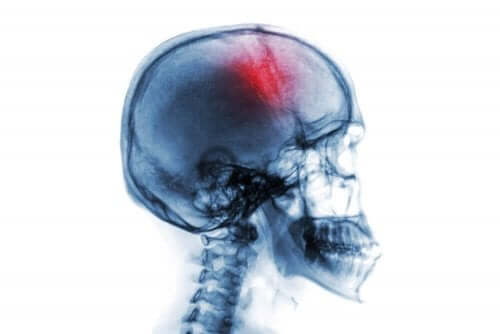

Aivohalvaus eli aivoverenkiertohäiriö on äkillinen neurologinen oireyhtymä, johon liittyy monia riskitekijöitä ja oireita. Siihen liittyy joko aivojen verenvuotoa tai verenkierron päättymistä.

Termi “aivohalvaus” voi viitata erilaisiin aivoverenkiertohäiriöihin. Näitä ovat mm. aivoverenvuoto, aivoinfarkti, ohimenevä aivoverenkiertohäiriö, jne.

- Aivohalvauksesta puhuttaessa tarkoitetaan verenvuodon lakkaamista aivoissa. Sen voi aiheuttaa ensin tukos aivoihin verta tuottavissa verisuonissa (iskemia). Tämä liittyy yleensä ateroskleroosiongelmiin. Toisekseen, se voi johtua aivojen sisäisestä verenvuodosta tai verenvuotohalvauksesta.